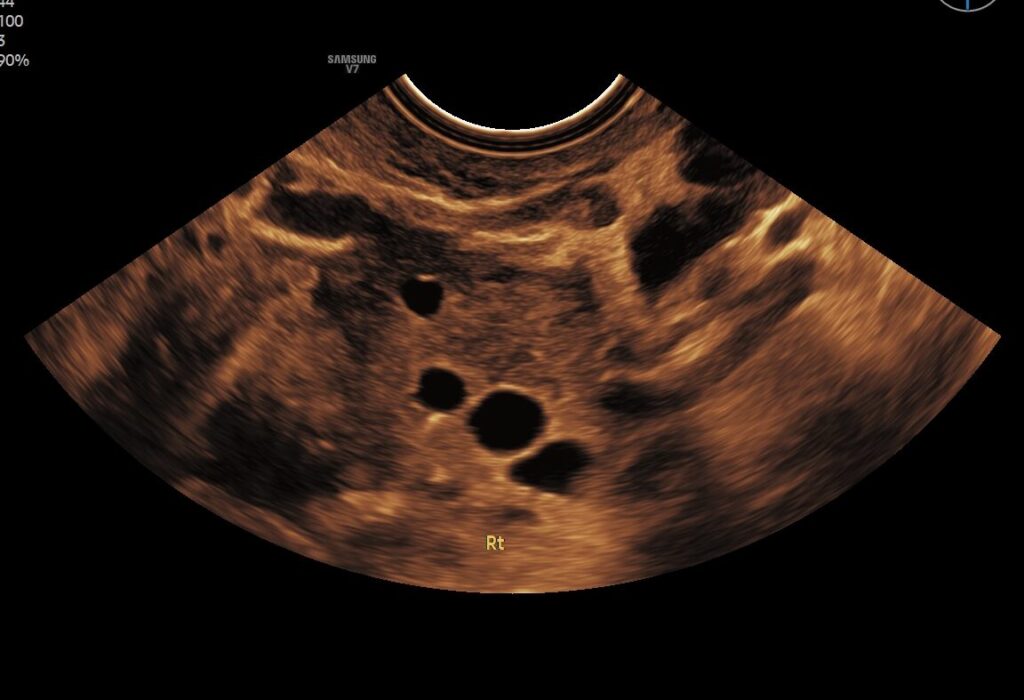

Medische echo’s

Professionele echo's die worden vergoed door de zorgverzekeraar. Mogelijk op doorverwijzing vanuit jouw zorgverlener.